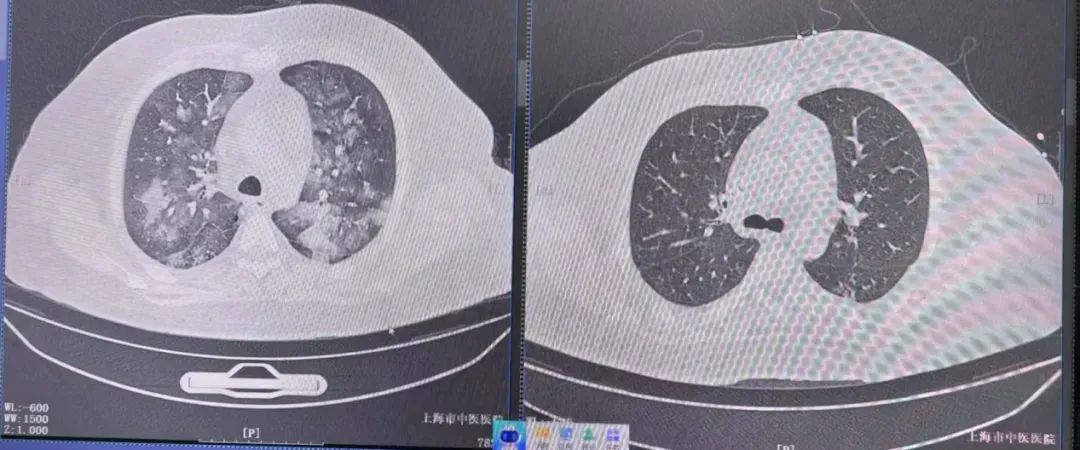

ICU团队结合以往的基础疾病和治疗情况,迅速抓住治疗的关键:患者流感病毒检测呈阳性,CT显示两肺呈“白肺”状变化——不能排除病毒性肺炎;结合患者长期使用尿毒症激素引起的免疫抑制,疑诊合并真菌感染;同时,患者在过去两个月内已经住院两次,不能排除革兰氏阴性菌和革兰氏阳性菌多种耐药感染的可能性。

治疗前后影像学变化明显。